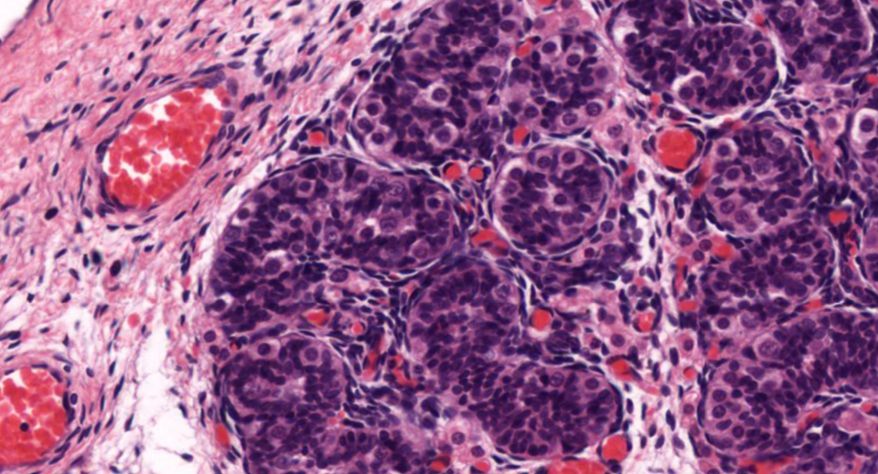

2 睾丸(新生儿)